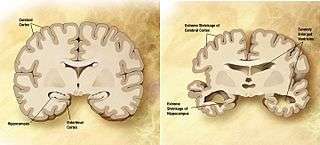

Comparison of a normal aged brain (left) and the brain of a person with Alzheimer's (right). Characteristics that separate the two are pointed out. | |

Alzheimer's disease is characterised by loss of neurons and synapses in the cerebral cortex and certain subcortical regions. This loss results in gross atrophy of the affected regions, including degeneration in the temporal lobe and parietal lobe, and parts of the frontal cortex and cingulate gyrus.[52] Degeneration is also present in brainstem nuclei like the locus coeruleus.[84] Studies using MRI and PET have documented reductions in the size of specific brain regions in people with AD as they progressed from mild cognitive impairment to Alzheimer's disease, and in comparison with similar images from healthy older adults.[85][86]

Both amyloid plaques and neurofibrillary tangles are clearly visible by microscopy in brains of those afflicted by AD.[87] Plaques are dense, mostly insoluble deposits of beta-amyloid peptide and cellular material outside and around neurons. Tangles (neurofibrillary tangles) are aggregates of the microtubule-associated protein tau which has become hyperphosphorylated and accumulate inside the cells themselves. Although many older individuals develop some plaques and tangles as a consequence of ageing, the brains of people with AD have a greater number of them in specific brain regions such as the temporal lobe.[88] Lewy bodies are not rare in the brains of people with AD.[89]